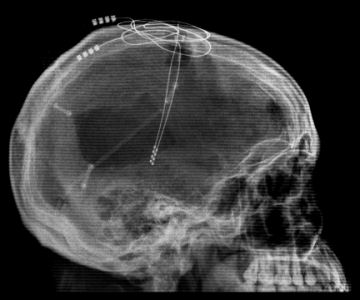

In a 10-hour operation, Rezai implanted two electrodes in the man’s thalamus, a bifurcated, walnut-shaped structure in the middle of the brain. The thalamus serves as the brain’s “grand central station,” says Rezai, as it relays signals from sensory organs and muscles to the cortex above.

Immediately after surgery, with the deep-brain stimulator sending signals into his thalamus, the man responded to voices and opened his eyes. After determining the device’s optimal settings, the team started a 6-month period during which the stimulator was turned on intermittently to allow evaluation of the man’s response. Physicians and therapists observing the man didn’t know whether the device was on or off. [To see an animated clip showing how deep brain stimulation works, click here. (17 MB .MOV file. Broadband connection strongly reccomended.)]